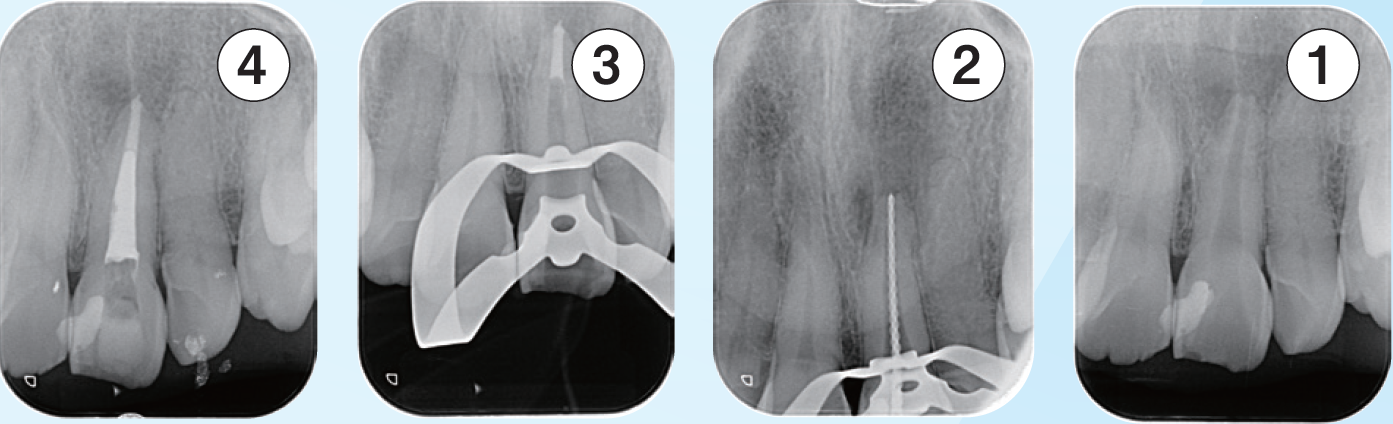

左上2番の感染根管処置

根中間部は狭窄しており根尖までは穿通障害歯である根中間部で異物を触知したため除去を行なった右は 、除去した破折ファイルを示す

臨床症例3 その3

①根管内の異物除去後のレントゲン像

②根中間部は狭窄しているものの細い号数のテーパーの少ないファイルで根尖までファイルを到達せせることができたのでEMRを測定しレントゲンを撮影した

③根尖は吸収度は少なく根尖孔径は#30で形成しガッタパーチャとMTAシーラーを用いて根管充填した

④根管充填後3ヶ月のレントゲン像

根尖周囲に見られた透過像の改善傾向が認められる